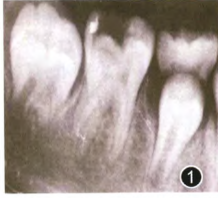

【辅助检查】

临床检查可见右下第一恒磨牙远中牙合面深大龋洞(见图1),可探及露髓孔,叩痛(±),患牙无松动,牙龈无异常,牙髓冷测试敏感。根尖x线片示根尖孔闭合,根尖周未见低密度影及根周膜增宽,未见根尖弯曲。

6个月复查时患者无不适,此时根尖x线片仍未观察到牙根的异常弯曲及穿孔,同时根尖周未见低密度影。